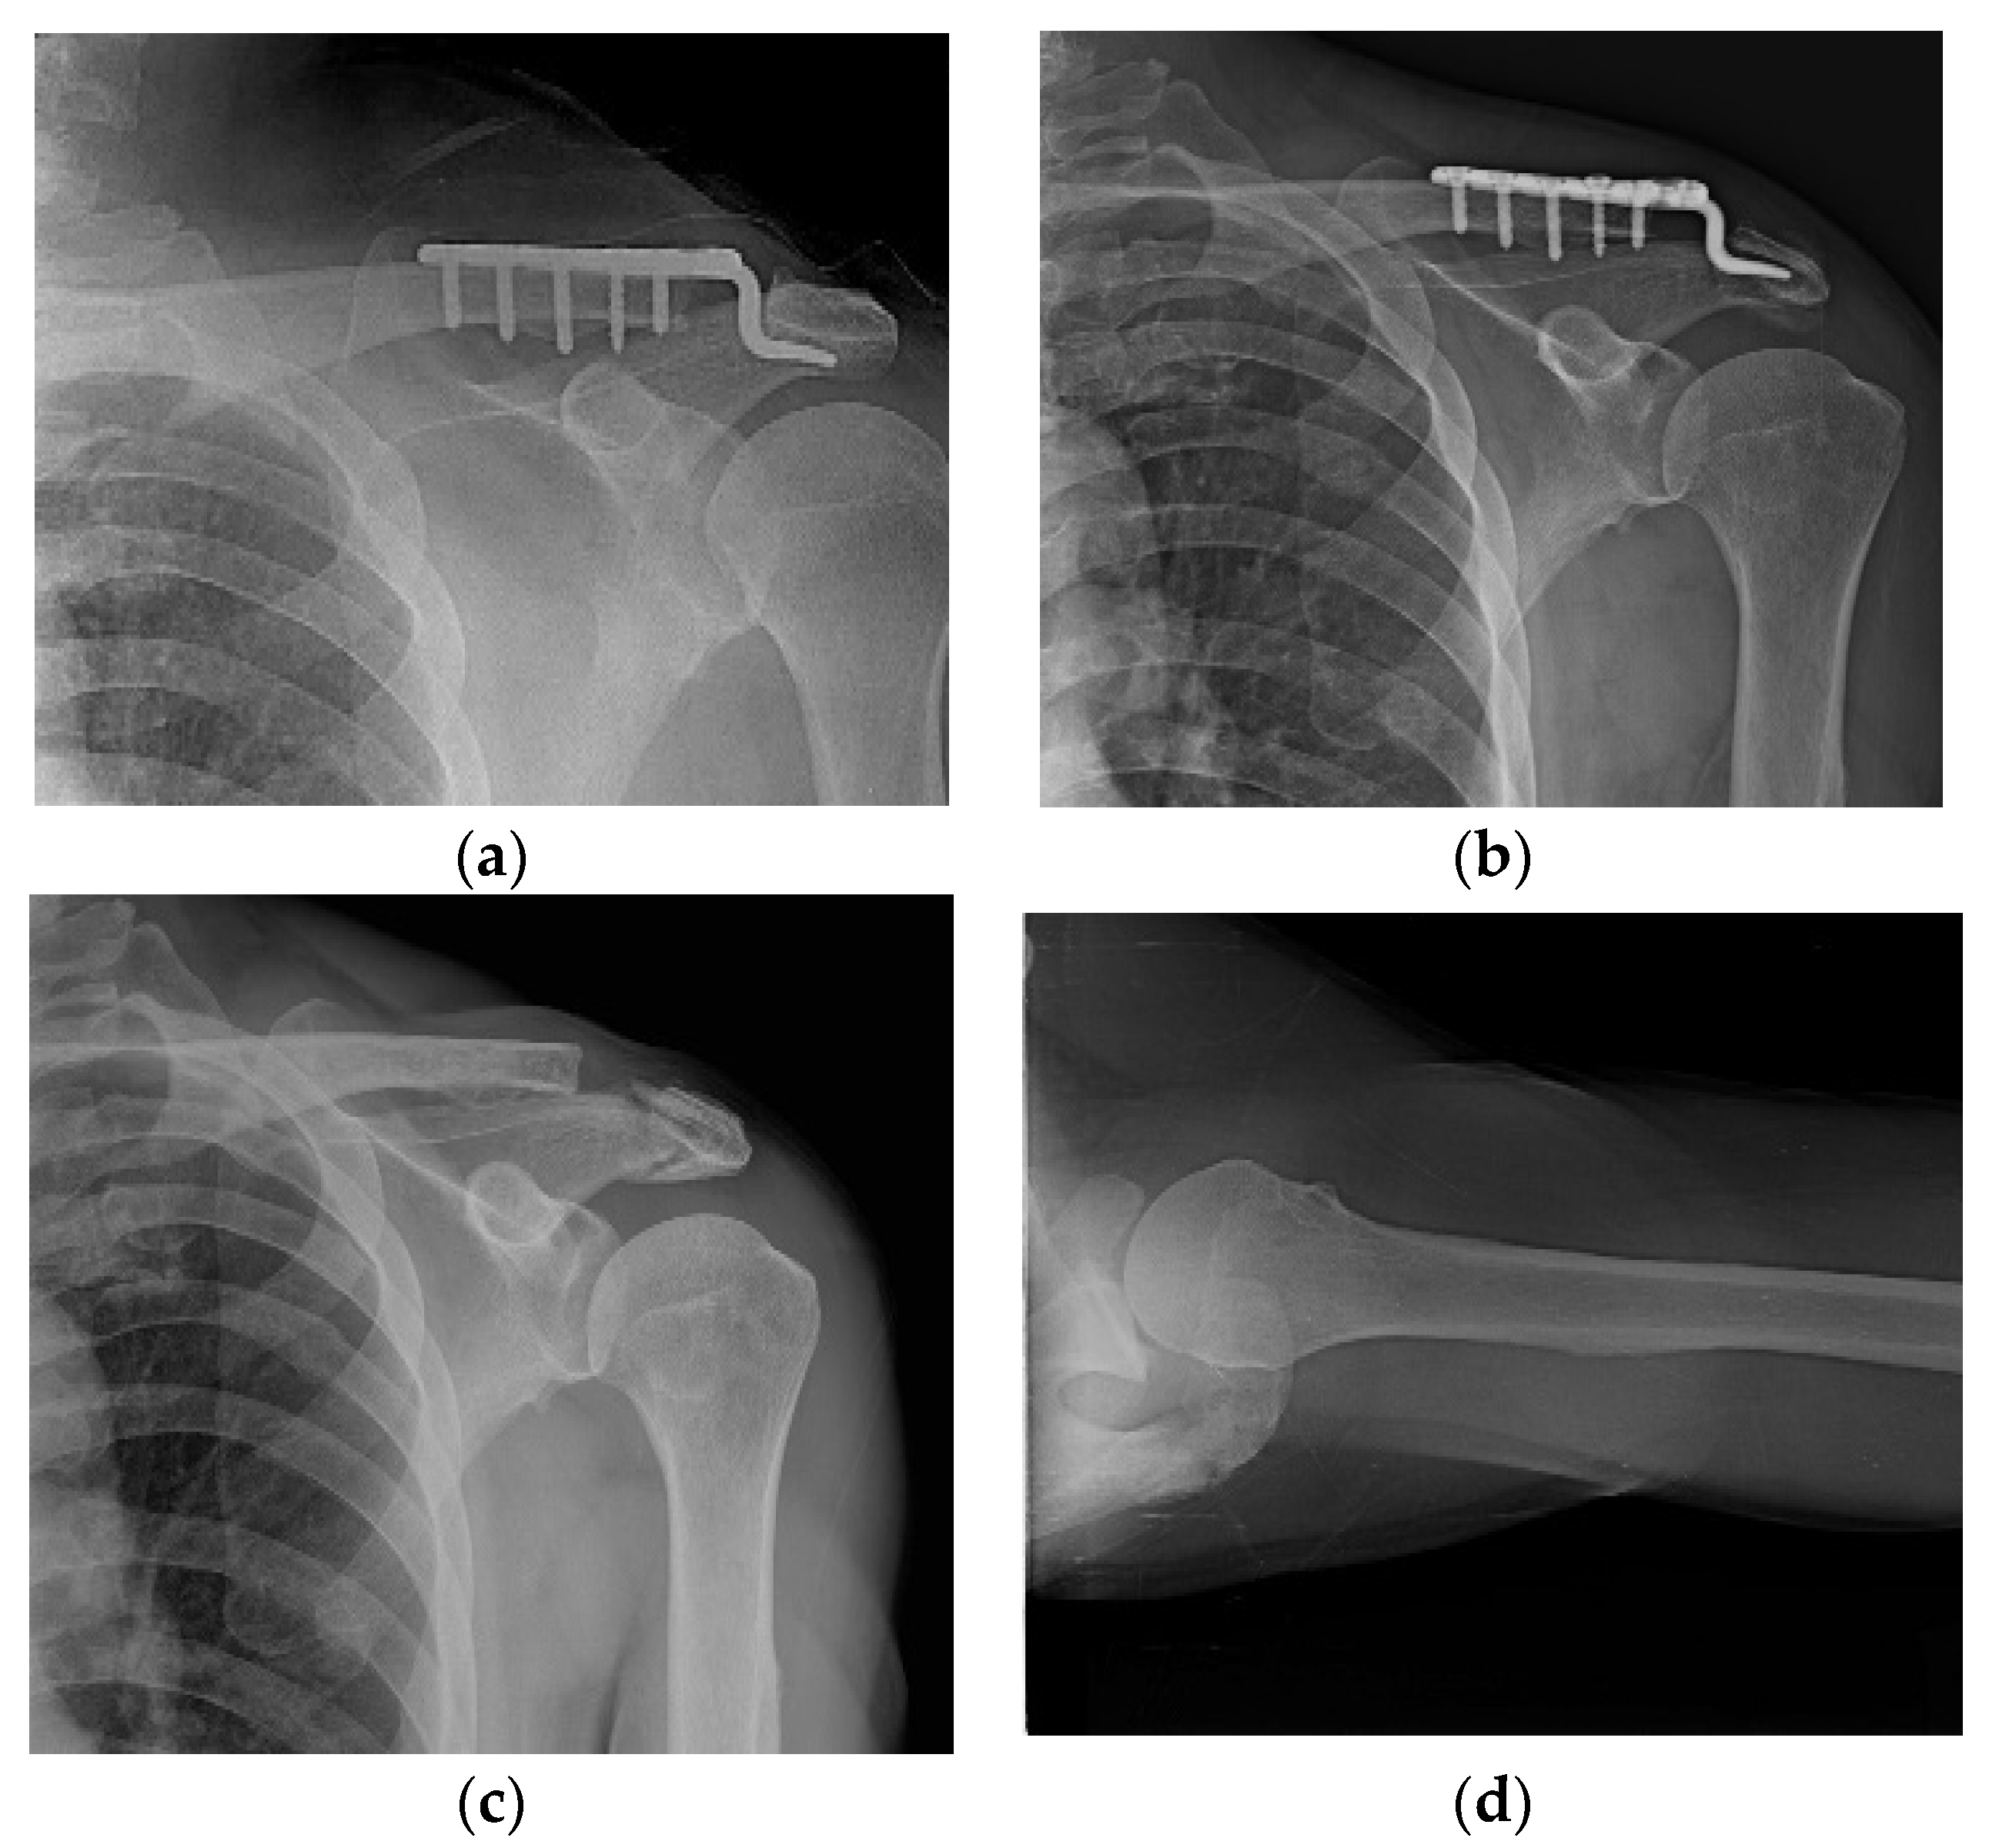

Varying degrees of subacromial erosion occurred in all patients, and acromial fracture occurred in one case in the DCF group and seven cases in the ACD group (Figure 2 and Figure 3). Five (6.7%) cases showed incomplete union and one (1.3%) case showed peri-implant stress fracture in the DCF group (Figure 4 and Figure 5). Four of the five cases of incomplete union showed fracture union without additional surgery during the follow-up period, and one case did not heal at the final follow-up, although the patient did not show any discomfort with non-union (Figure 6). The peri-implant fracture healed with conservative management before plate removal. LOR was observed in nine patients with ACD. Before removing the hook plate, LOR occurred in six patients with ACD. Among these six patients, five showed acromial fracture and one showed serious subacromial erosion (Figure 7). After removing the hook plate, LOR occurred in three patients during the follow-up period. However, none of these patients with LOR among patients with ACD showed tenderness on the acromioclavicular joint or pain during the follow-up period. Regarding acromial fracture, one (1.3%, 1 of 36) case was observed in the DCF group and seven (8.3%, 7 of 33) cases were noted in the ACD group (Figure 4). There was no difference in the incidence of acromial fracture between patients with DCF and ACD (p = 0.066). All eight patients had fracture union without additional surgical treatment during the follow-up period.

Figure 4. Incomplete union. (a) A 57-year-old male patient 4 months after hook plate fixation. (b) The plate is removed after incomplete union on patient request. (c) Bone union is achieved during follow-up.

Figure 5. Peri-implant fracture. A 76-year-old female patient who underwent AO-type hook plating in the DCF group. (a) Postoperative clavicle anteroposterior radiograph view. (b) Patient showing peri-implant fracture on midshaft area of clavicle during the follow-up period of 4 months. (c) After removing the hook plate during the follow-up period, bone union is achieved.

Figure 6. The only case of non-union among five incomplete union cases. (ac) A 50-year-old male patient is fixed with a hook plate and bone union is not completed at 4 months, but severe painful shoulder stiffness is noted; therefore, manipulation is performed while removing the metal plate. (d) Bone union does not occur during the follow-up period.